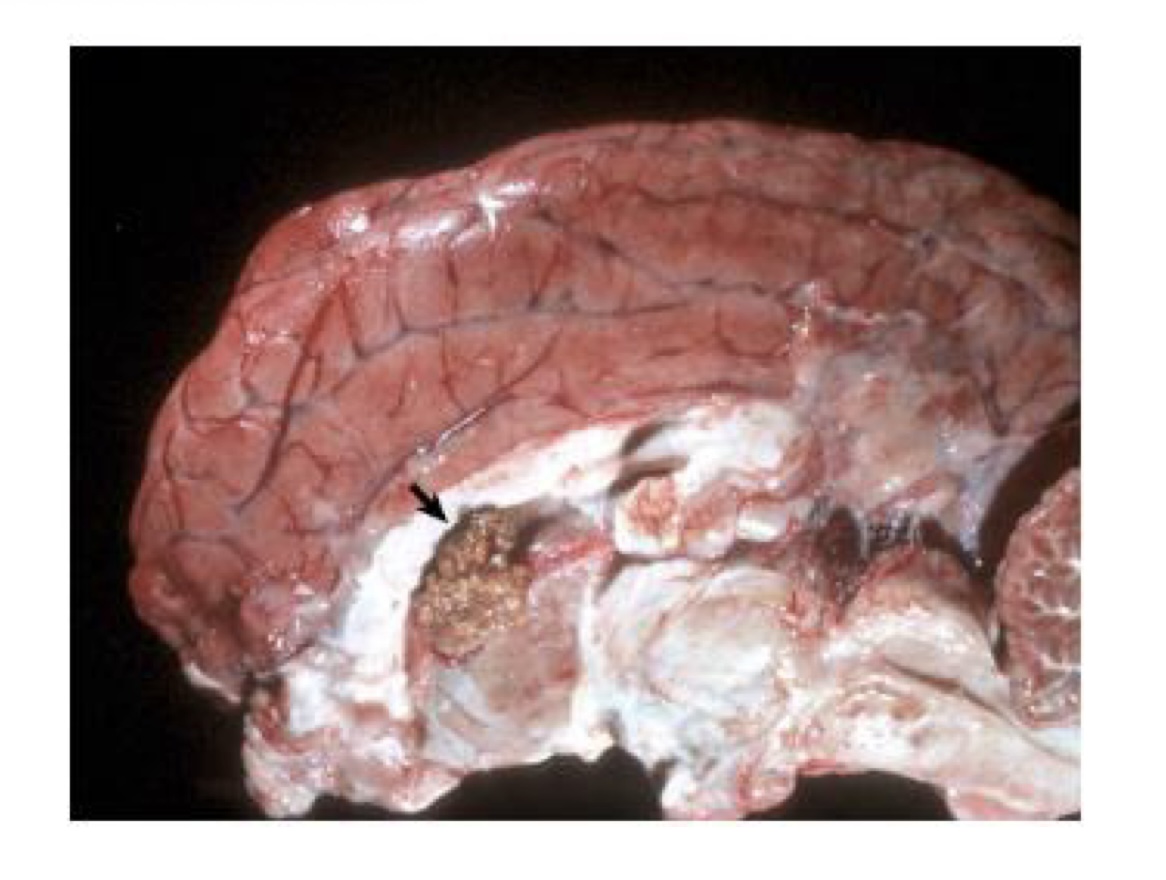

what is this?

metastatic hemangiosarcoma → prominent hematogenous metastases, which appear as black nodules of various sizes distributed throughout the brain

in an unfixed specimen, what color would the nodules of metastatic hemangiosarcoma be?

red to dark red